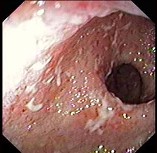

(单选题)肠镜检查如图,病理示固有膜内弥漫性淋巴细胞、浆细胞、单核细胞浸润,最可能的诊断为()。

A:Crohn病

B:肠结核

C:肠伤寒

D:梅克尔憩室

E:溃疡性结肠炎